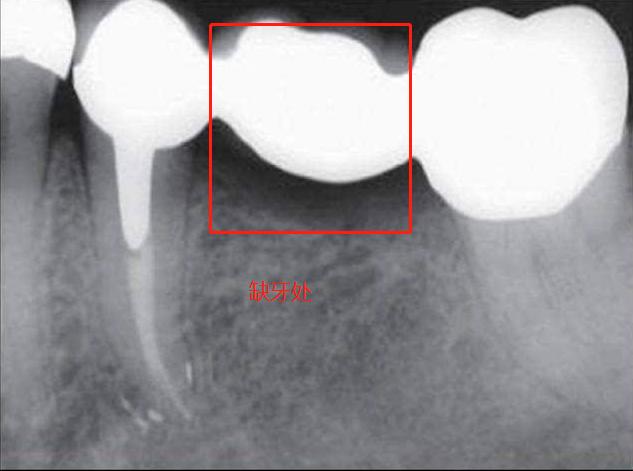

长时间佩戴固定桥,缺牙部位因为身体原因出现了牙龈萎缩等情况,对导致固定桥的密封性出现问题,引发两侧天然牙龋坏。有统计数据表明,佩戴固定桥十年左右,基牙龋坏的比例高达百分之三十。